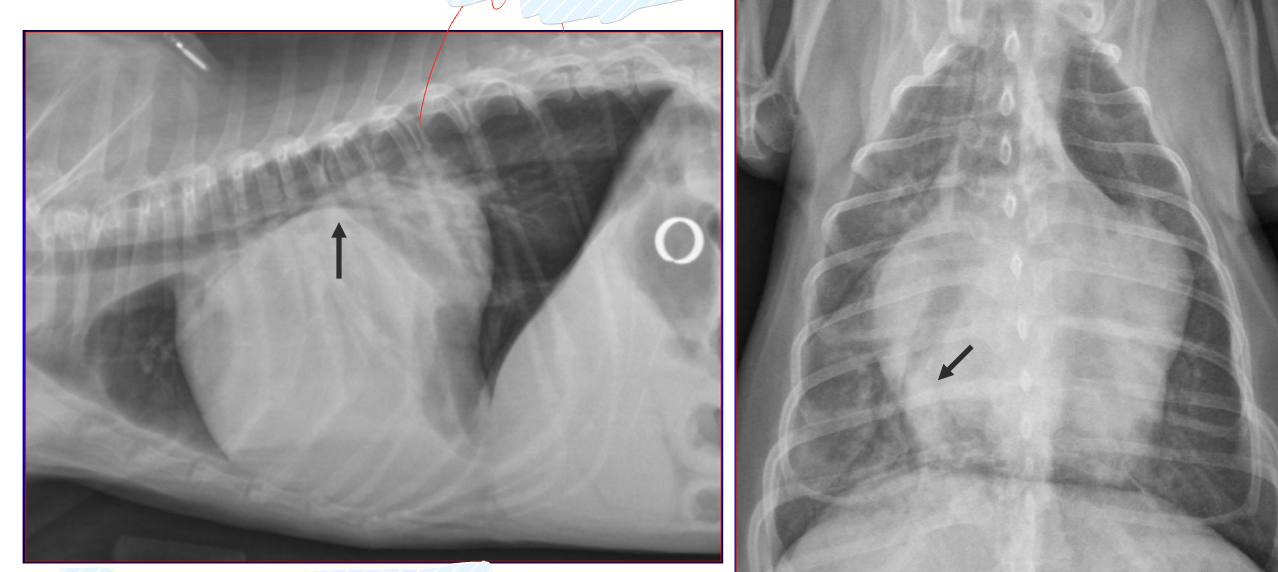

which of the following is a more appropriate radiograph

Upper left- inspiration- more space between heart and diaphragm

Lower right: exhalation- not as much space